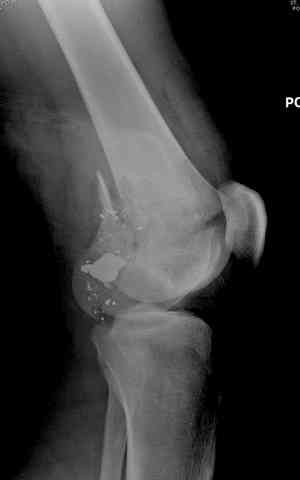

Пуля от ПМ - очевидно, что ранение было т.н. низкоэнегетическим, что подтверждается в том числе спокойным состоянием мягких тканей в этом, уже отсроченном периоде.

Однозначно, огнестрельные переломы стоит стабилизировать АНФ в максимально ранние сроки после получения ранения. Так же при ПХО или повторной ХО требуется фасциотомия. Эти две манипуляции приводят к улучшению паравульнарного кровотока и уменьшают вероятность развития вторичных осложнений. Дождавшись закрытия ран и при полной уверенности в отсутствии гнойных осложнений можно поднимать вопрос о конверсии наружного остеосинтеза на внутренний. Судя по снимку, пуля пистолетная, перелом не носит многооскольчатый характер, что дает основание полагать, что невысокая энергия ранения подразумевает невысокую вероятность вторичных осложнений и возможность внутреннего остеосинтеза. Конечно, БИОС в а\б муфте предпочтительнее ввиду щадящего отношения к кровообращению в заинтересованной области, но лучшая методика та, которой хорошо владеет хирург.

Характерным признаком травмы с низкой кинетической энергией является отсутствие "мультифрагментации и кавитации", и поэтому в данном случае лечение можно проводить любым доступным методом.

Здесь представлены несколько случаев лечения огнестрельного перелома

2 внутрисуставной перелом дистального бедра с удалением пули